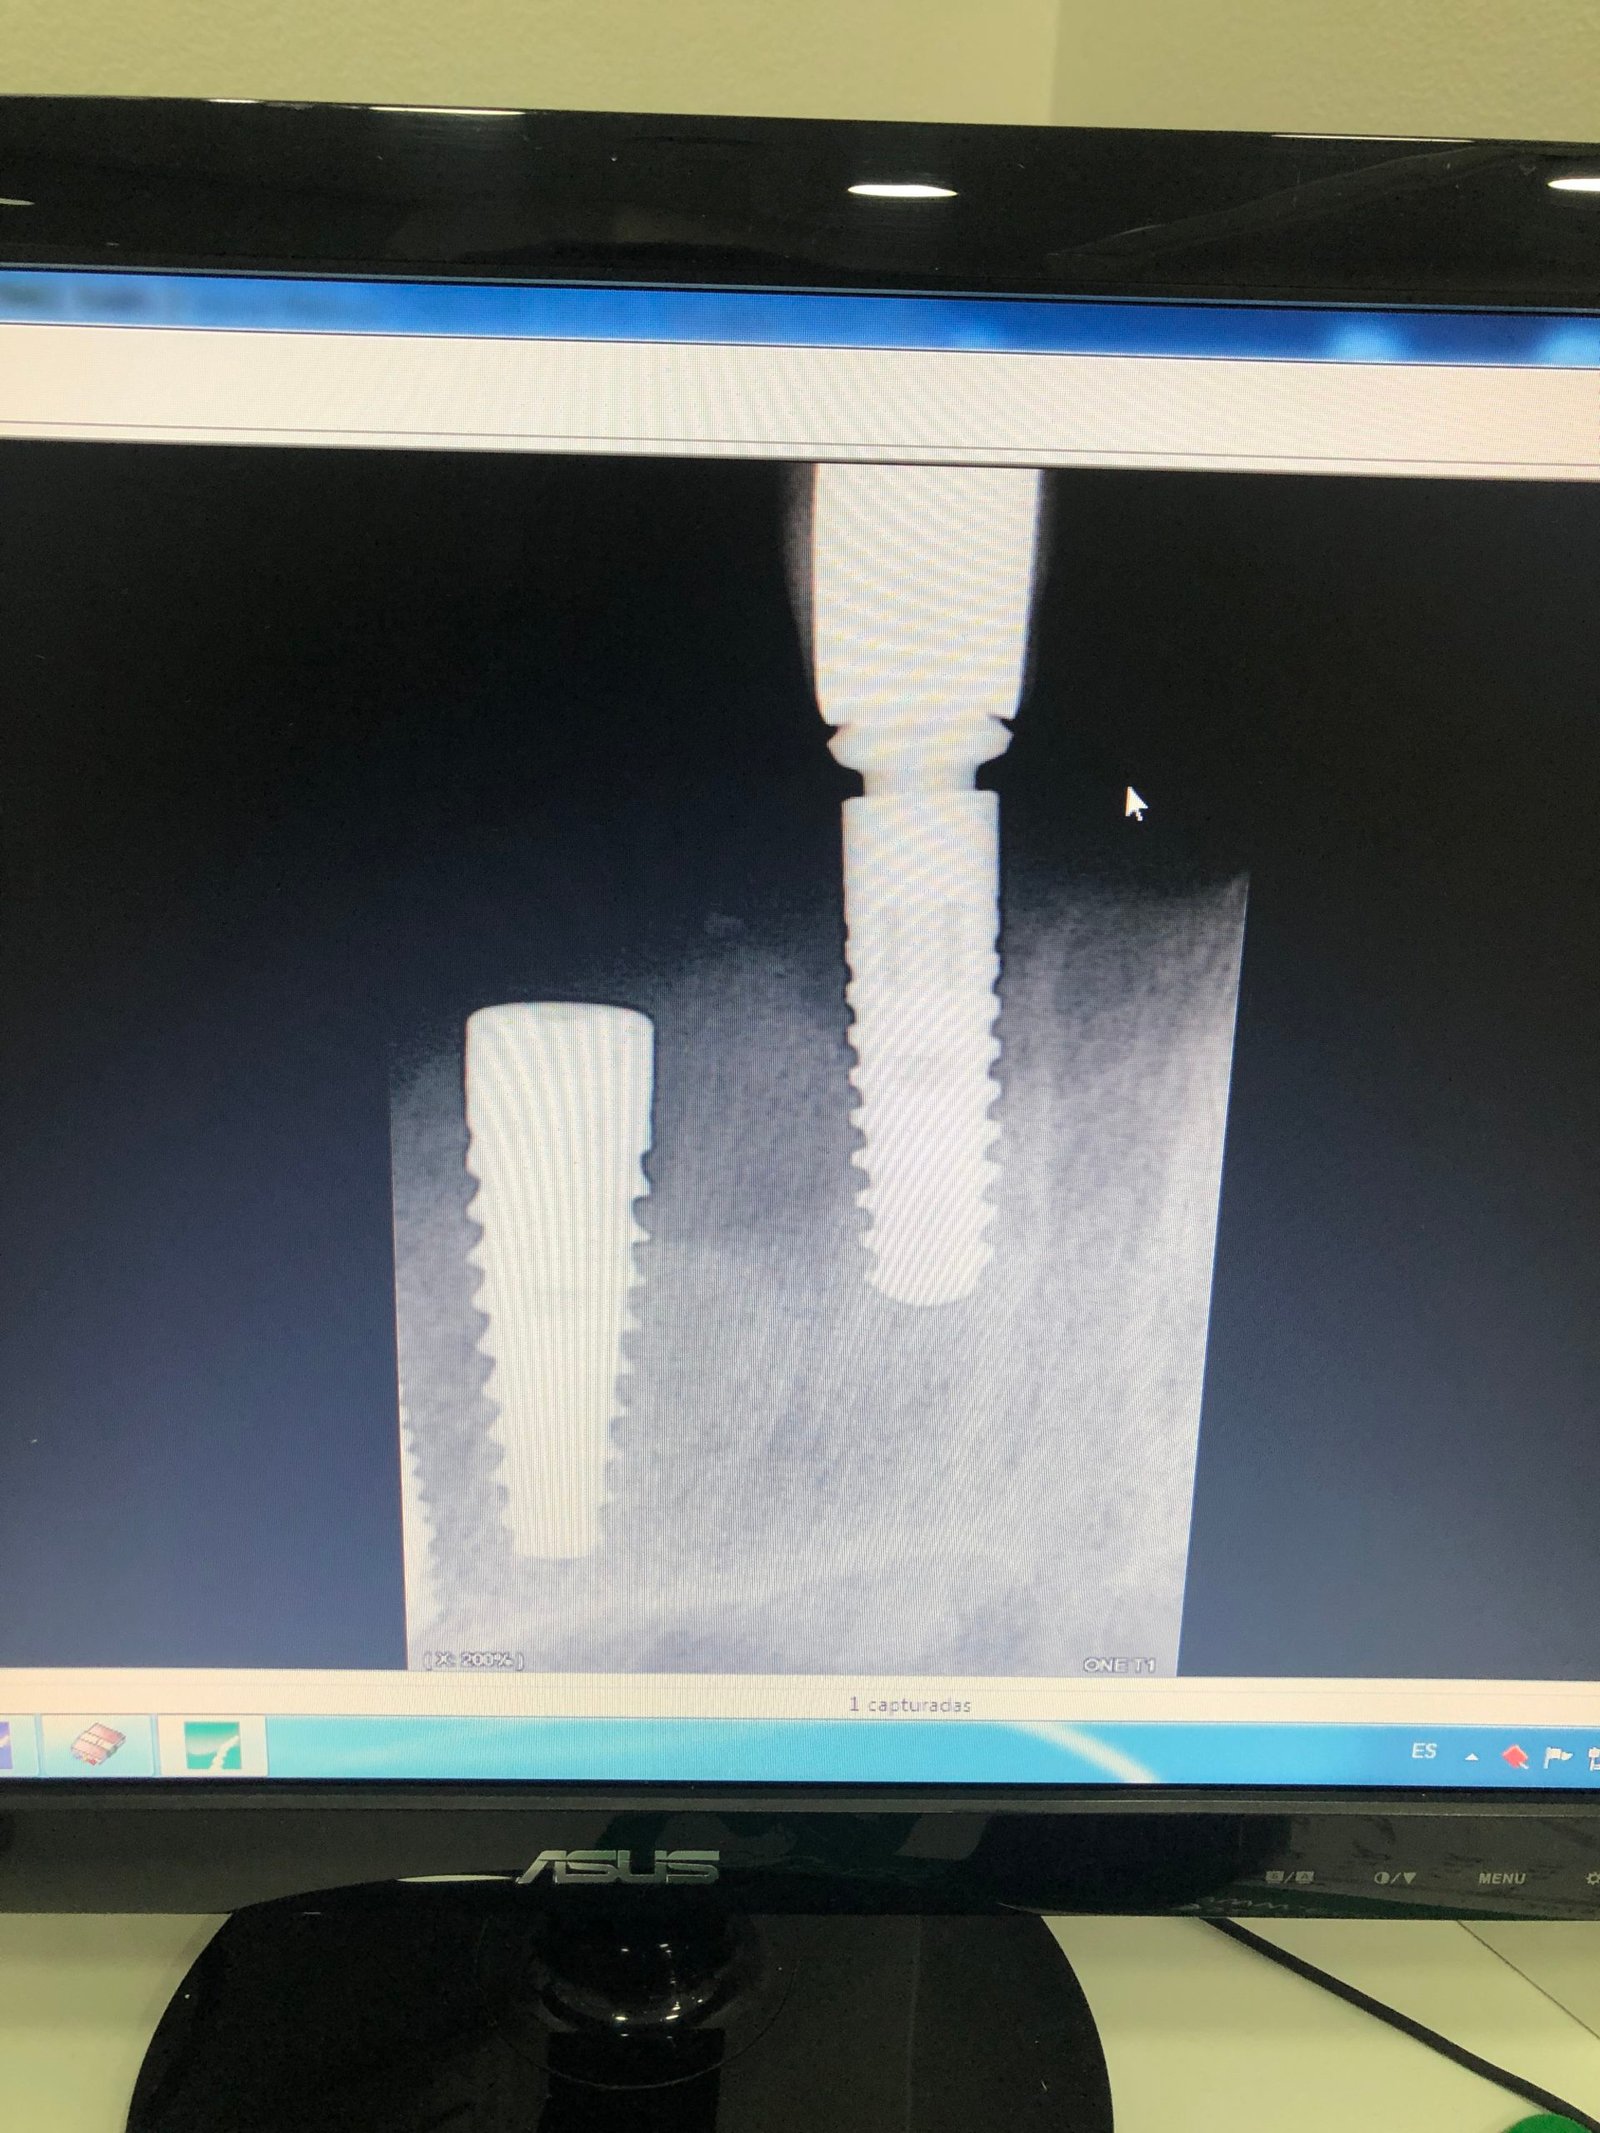

Identificar implantes

Necesito identificar para rehabilitar